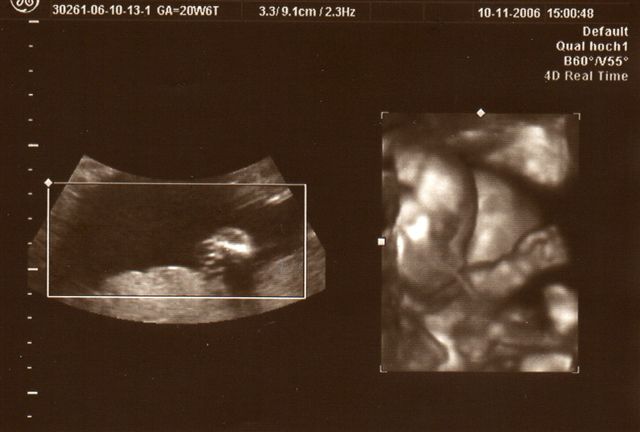

Ich war beim "Partner"-Doc der Gemeinschaftspraxis, in die mein Doc seit Juli eingestiegen ist. Dieser ist ebenfalls supernett und hat zudem noch ein 3D-Ultraschall, welches er mit auch gezeigt hat, nachdem er mit dem normalen Ultraschall alles "kontrolliert" hat. Es ist immer noch alles dran, ist alles zeitgerecht entwickelt. Nach der Gesamtgröße hab ich gar nicht gefragt, aber das Köpfchen hat 13 cm Umfang. Das ist genau Golfballgröße. Zum guten Schluss hat er mir dann noch ein 3D-Bild mitgegeben, auf dem man ohne Erklärung noch nicht wirklich viel erkennen kann. Das liegt u.a. auch daran, dass Krümel noch nicht genug Speck auf den Rippen hat und sich immer weggedreht ha - nicht ohne uns vorher zuzuwinken

Wieder war ich beim "Partner-Doc". Dieses Mal stand das 2. Screening an, das um die 20. Schwangerschaftswoche herum gemacht wird. Wahrscheinlich hätte "mein" Doc seinen Partner eh gebeten dies durchzuführen, weil er das modernste Gerät hat. Ich hab dann so nebenbei erfahren, dass er wohl der einzige Doc in Düsseldorf ist neben dem Praenatal-Zentrum und der Diakonie, der dieses Ultraschallgerät besitzt. Was ich bzw. wir bei diesem großen Ultraschall zu sehen bekommen haben, war umwerfend und zugleich auch ein bißchen erschreckend - erschreckend nicht, weil mit Krümel etwas nicht in Ordnung ist, sondern weil man so unglaublich viel sehen kann, also positiv erschreckend. Jedenfalls ist alles in bester Ordnung. Jedes Organ ist da wo es hingehört und funktioniert so wie es funktionieren sollte, nichts fehlt. Krümel ist zudem zeitgerecht entwickelt, sehr beweglich und aktiv. Außerdem lag Krümel so günstig, dass der Doc zwischendurch auf 3D bzw. 4D-Realtime umschalten konnte und wir so faszinierende Bilder gesehen haben. Die schönsten hat er mit ausgedruckt. Eines davon seht ihr oben. Und einen Fuß hat er noch "eingefangen". Der Kopfumfang ist seit dem letzten Mal um fast 3 cm gewachsen und Krümel ist insgesamt geschätzt 16 cm lang, wobei dies ein reiner Schätzwert ist und sowohl nach unten, eher aber nach oben abweichen kann. Ich bin sooo glücklich dass alles in Ordnung ist. Lars´ Augen haben beim Anblick der "Fotos" geleuchtet und meinte: "Mami, ich hab das Baby sooooo lieb!"

So und nu zeig ich noch das "Fuß-Foto" :